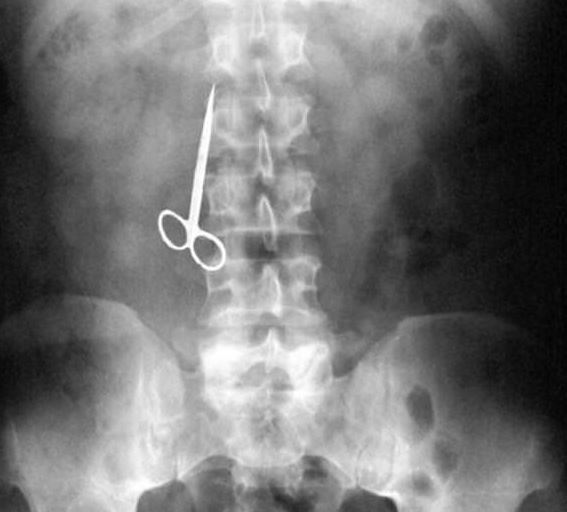

Doktorların görüp yok artık bu nasıl mümkün olur dedikleri röntgen filmleri..

Doktorluğun zor bir meslek olduğu malum. Üstelik bu mesleğin icra ederken bazı zamanlar öyle vakalar ortaya çıkmış ki, doktorlar bile anlamlandırmakta zorluk çekmişler.